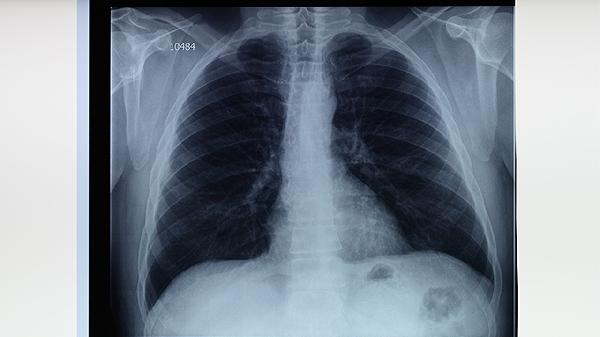

中醫(yī)治療肺結(jié)核需堅持服藥3-6個月,期間定期復查胸部影像學。飲食宜高蛋白、高維生素,可食用銀耳羹、雪梨川貝湯等藥膳。注意隔離消毒,避免劇烈運動,保證充足睡眠。若出現(xiàn)大咯血或持續(xù)高熱,應立即中西醫(yī)結(jié)合救治。所有中藥均須在執(zhí)業(yè)中醫(yī)師指導下使用,不可自行調(diào)整劑量。